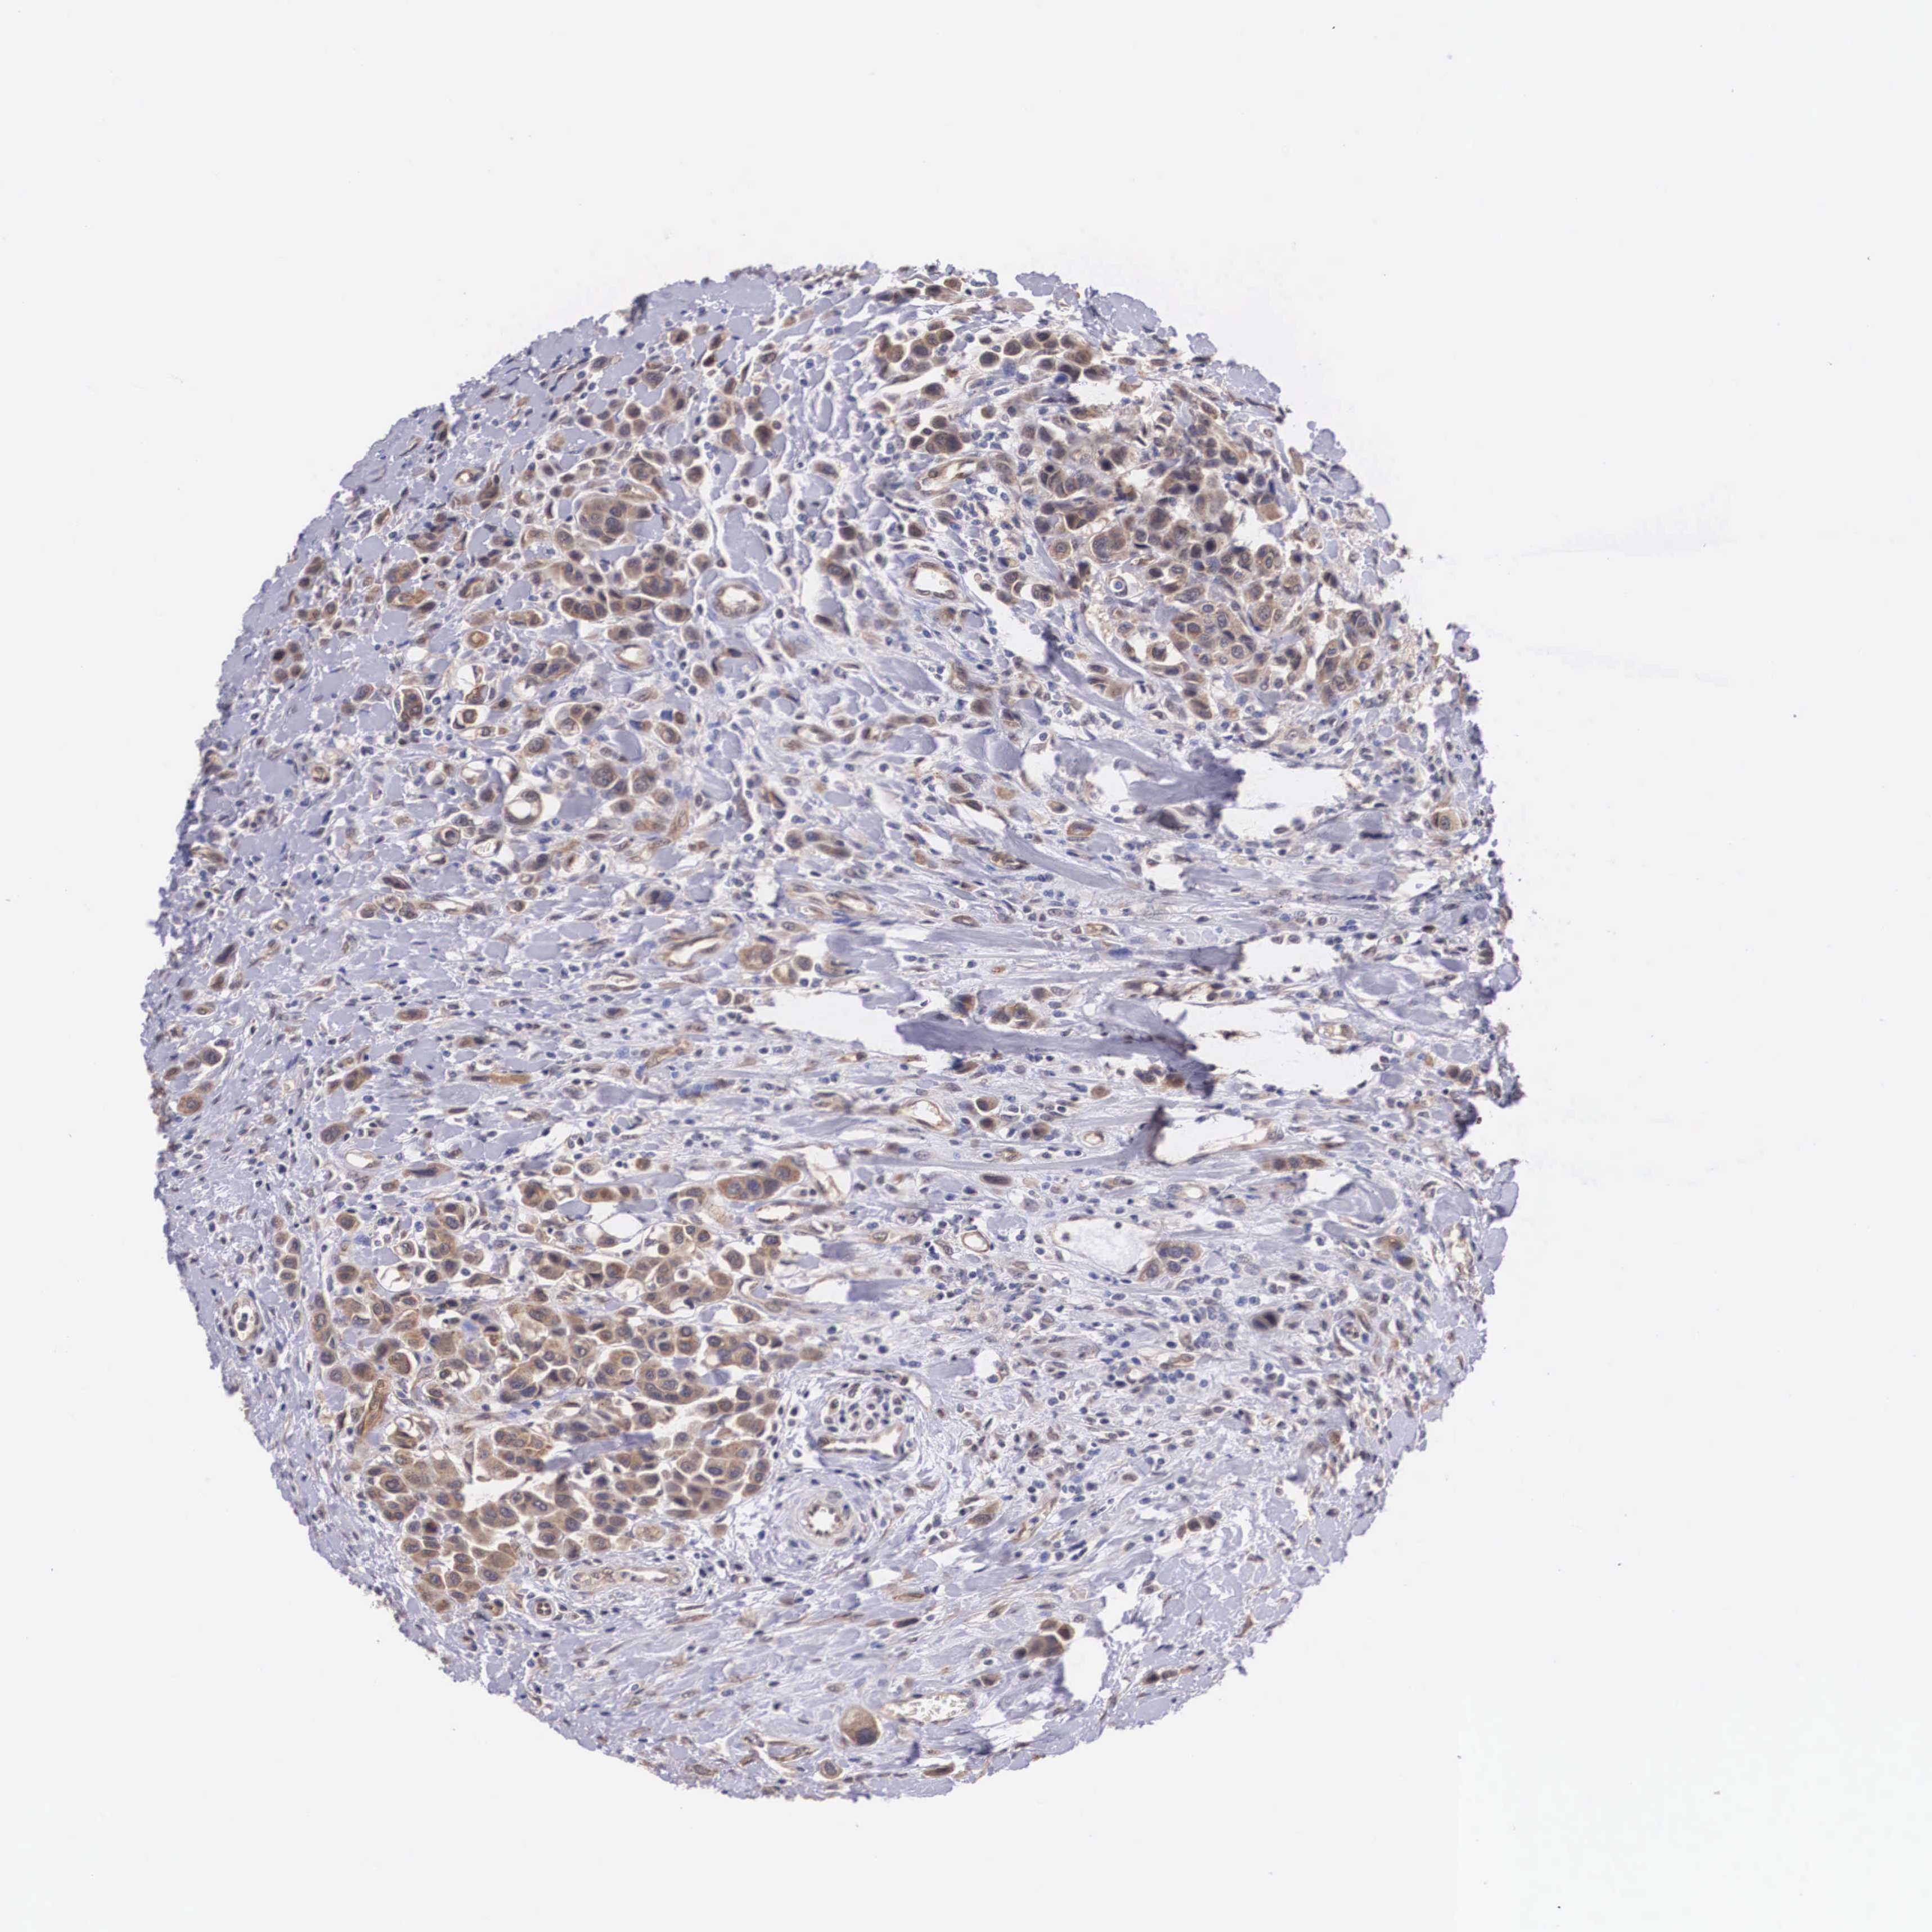

UROTHELIAL CANCER - Protein expressioni

A mouse-over function shows sample information and annotation data. Click on an image to view it in a full screen mode. Samples can be filtered based on level of antibody staining by selecting one or several of the following categories: high, medium, low and not detected. The assay and annotation is described here.

Note that samples used for immunohistochemistry by the Human Protein Atlas do not correspond to samples in the TCGA dataset.

Antibody stainingi

Antibody staining in the annotated cell types in the current human tissue is reported as not detected, low, medium, or high, based on conventional immunohistochemistry profiling in selected tissues. This score is based on the combination of the staining intensity and fraction of stained cells.

Each image is clickable and will lead to virtual microscopy that enables deeper exploration of all samples and also displays staining intensity scores, fraction scores and subcellular localization as well as patient and tissue information for each sample.

Antibody HPA000633

Staining

High

Medium

Low

Not detected

Intensity

Strong

Moderate

Weak

Negative

Quantity

>75%

75%-25%

<25%

None

Location

Nuclear

Cytoplasmic/membranous

Cytoplasmic/membranous,nuclear

Urothelial carcinoma, High grade